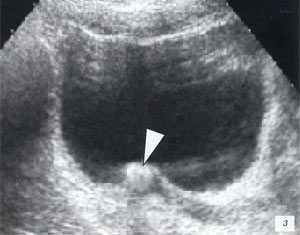

Доброкачественная гиперплазия предстательной железы.